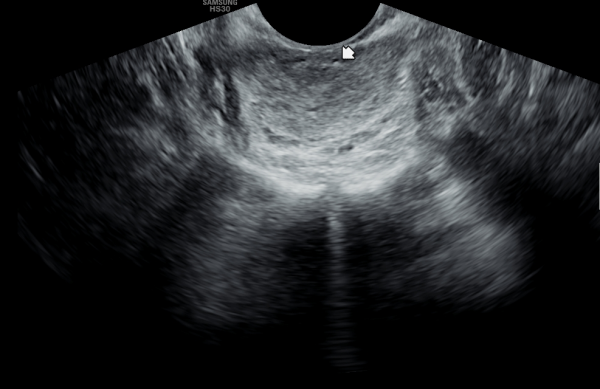

전립선의 표적치료후 고환의 미석증이 없어지고 고환이 커진 경직장 전립선 초음파 자료 입니다.(주2회 표적치료)

This is a transrectal ultrasound image showing the improvement after targeted prostate treatment.

After twice-weekly targeted treatment, testicular microlithiasis disappeared, and the testicles increased in size.